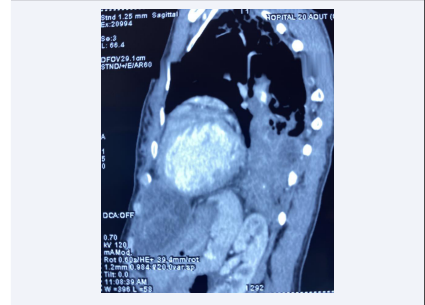

In our patient, the paravertebral hydatid cyst was asymptomatic, discovered on thoracic CT [Figure 1 and Figure 2].

Frontal section of thoracic tdm showing left pulmonary  hydatid cysts with a homolateral paravertebral hydatid cyst.

Figure 1: Frontal section of thoracic tdm showing left pulmonary hydatid cysts with a homolateral paravertebral hydatid cyst

Sagittal section of thoracic tdm showing left pulmonary  hydatid cysts with a homolateral paravertebral hydatid cyst.

Figure 1: Sagittal section of thoracic tdm showing left pulmonary hydatid cysts with a homolateral paravertebral hydatid cyst.